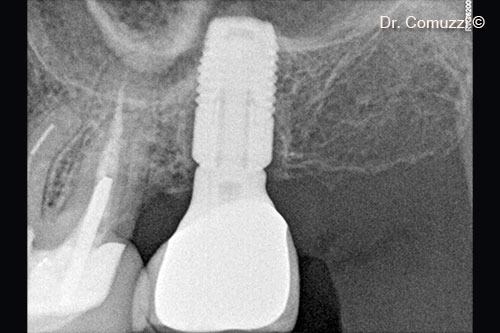

6. X-ray of Sinus Lift at implant placement